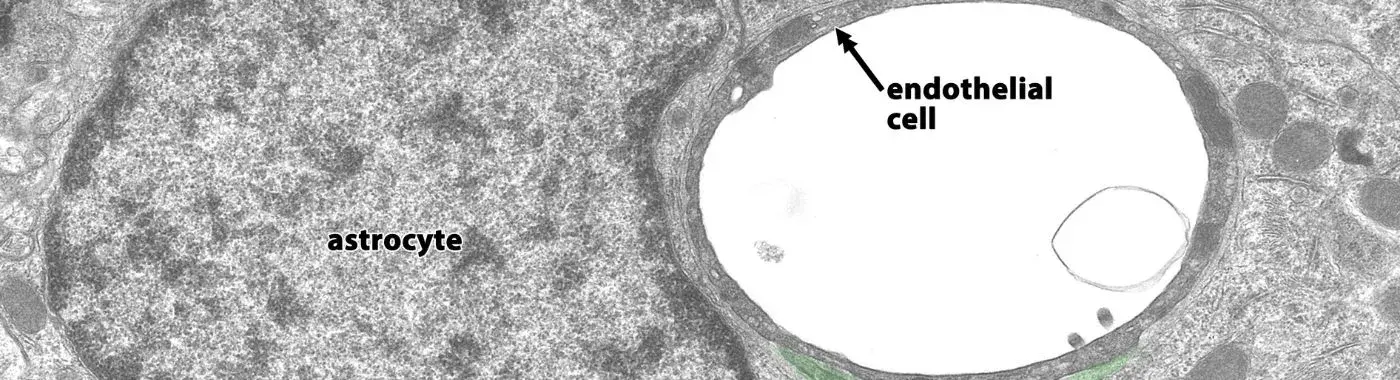

Endothelial dysfunction refers to a state in which the endothelium—the thin layer of cells lining the blood vessels—fails to function normally. This dysfunction can result in an imbalance between vasodilating and vasoconstricting substances, leading to impaired blood flow and increased vascular resistance. The endothelium plays a crucial role in maintaining vascular health by regulating blood pressure, blood clotting, and immune function. When it becomes dysfunctional, it can contribute to the development of atherosclerosis, hypertension, and other cardiovascular diseases.